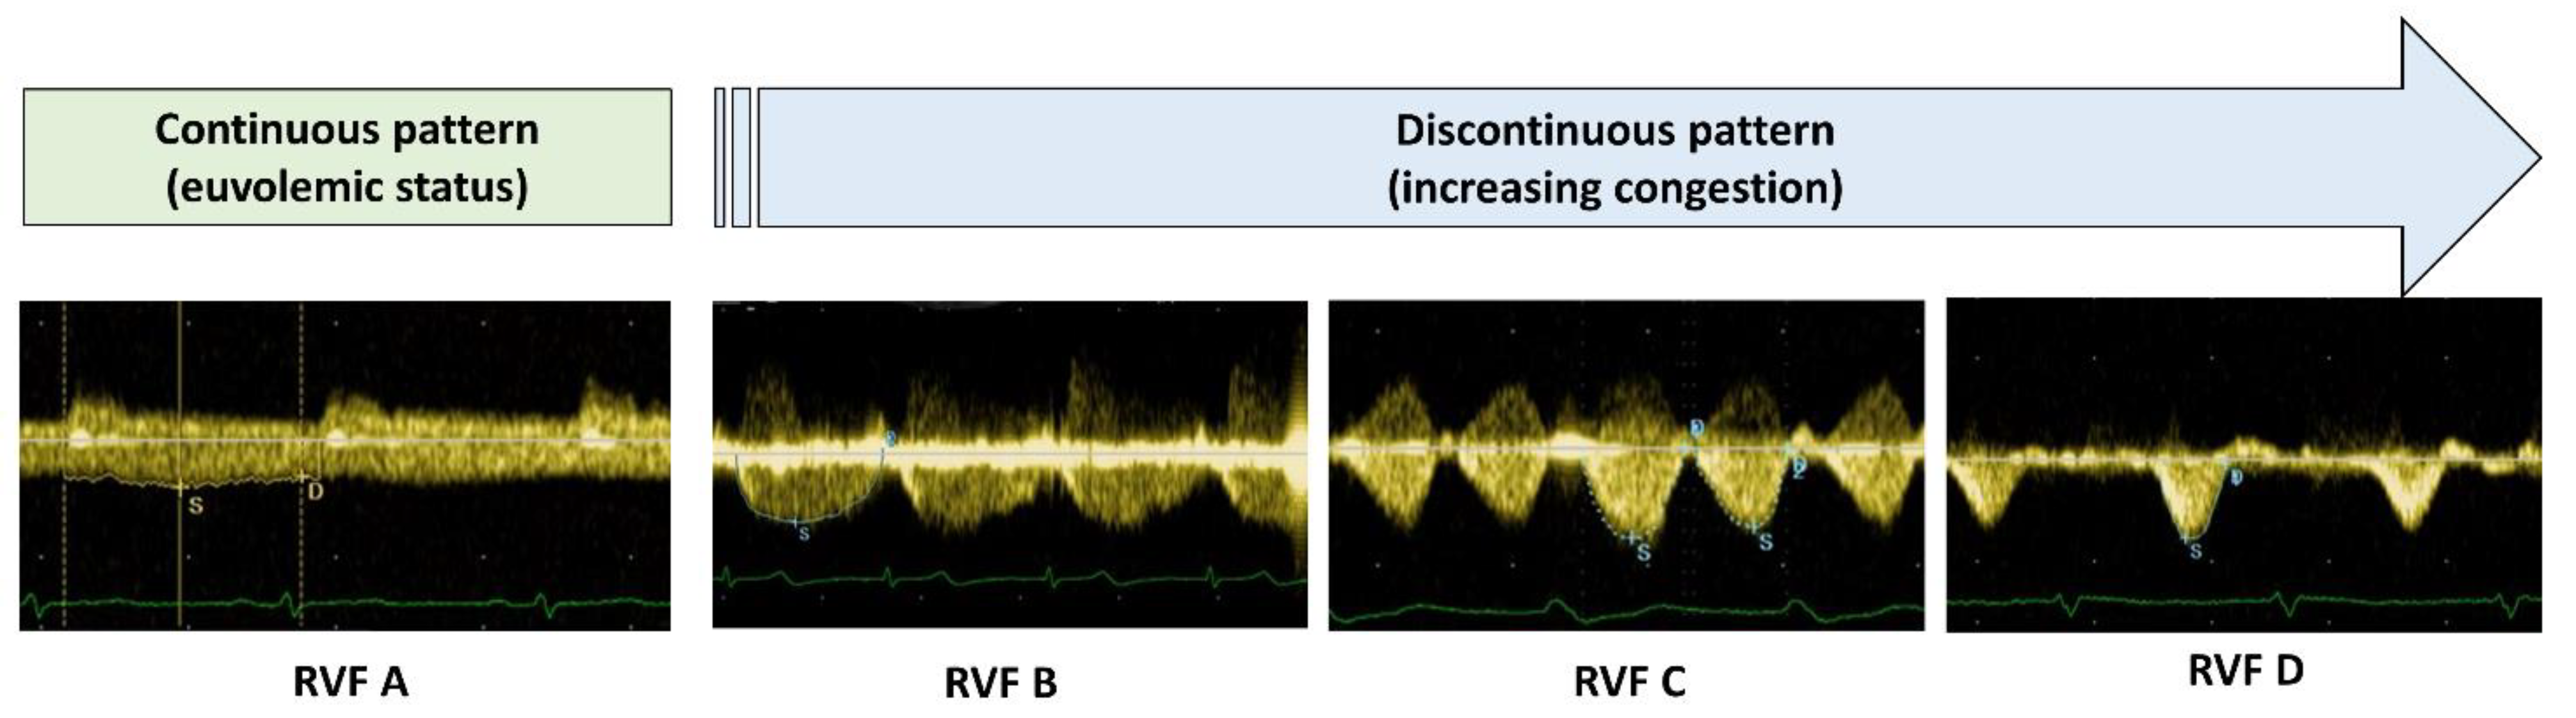

| Variable | RVF A (n = 230) | RVF B (n = 39) | RVF C (n = 18) | RVF D (n = 17) | p-Value |

|---|---|---|---|---|---|

| NT-proBNP §, ng/L | 332 (160–918) | 768 (379–1522) * | 1520 (783–2550) * | 2147 (1427–4172) *^° | <0.0001 |

| uACR, mg/g | 15 (8–53) | 22 (8–63) | 26 (13–65) | 38 (27–121) * | 0.03 |

| Serum creatinine, mg/dL | 0.93 (0.79–1.18) | 0.96 (0.92–1.25) | 1.08 (0.93–1.25) | 1.14 (0.96–1.39) * | 0.03 |

| Average E/e’ | 10.5 (8.1–14.1) | 12.7 (10.1–16.7) | 13.1 (8.8–18.6) | 15.8 (10.2–21.3) * | 0.003 |

| LAVi, mL/m2 | 40 ± 14 | 49 ± 16 * | 50 ± 13 * | 60 ± 18 *^ | <0.0001 |

| Systolic PAP, mmHg | 34 ± 11 | 44 ± 16 * | 49 ± 17 * | 54 ± 13 *^ | <0.0001 |

| ePVR, WU | 1.5 ± 0.8 | 1.8 ± 0.9 | 2.1 ± 1.0 | 2.4 ± 1.1 * | 0.016 |

| ePAWP, mmHg | 10.0 ± 3.5 | 14.5 ± 5.9 * | 15.7 ± 5.8 * | 21.2 ± 5.8 *^° | <0.0001 |

| IVC, mm | 15 (15–18) | 18 (15–20) * | 20 (18–22) * | 27 (25–31) *^° | <0.0001 |

| B-lines | 1 (0–4) | 3 (0–10) | 6 (1–15) * | 10 (1–18) * | <0.0001 |

| TAPSE/sPAP | 0.64 ± 0.23 | 0.52 ± 0.24 * | 0.43 ± 0.17 * | 0.36 ± 0.10 *^° | <0.0001 |